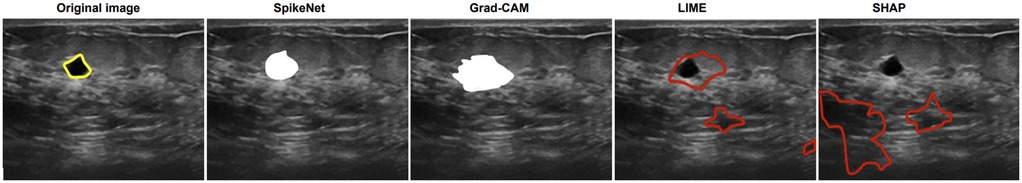

We compare explanation methods using the XAlign metric, which scores spatial alignment between saliency maps and expert annotations. To control for backbone effects, all post hoc methods (Grad-CAM, LIME, SHAP) are applied to the SpikeNet classifier with the native explanation head disabled and target the last convolutional block for Grad-CAM. The row labelled SpikeNet (native) reports the integrated explanation head with the head enabled. All results follow the same preprocessing and patient-level evaluation protocol. Each figure illustrates the explanation maps generated for a representative image, accompanied by the expert-annotated tumour boundary (yellow). Additionally, XAlign scores are reported to quantitatively measure the alignment between the saliency maps and ground truth. Tables 1114 report XAlign for representative MRI and ultrasound cases; dataset-level means with standard deviations and paired tests are provided in Table 15 later in this section.

In the final case (Figure 4), SpikeNet once again provides the most faithful explanation, with Grad-CAM trailing due to boundary spillover. LIME and SHAP continue to underperform with disjointed, inaccurate highlights. As seen in Table 14, SpikeNet attains the highest XAlign score (0.927), further confirming its robustness across modalities.

Figure 4

Five ultrasound images compare different segmentation methods. The original image highlights a region in yellow. SpikeNet and Grad-CAM emphasize a white area. LIME and SHAP use red outlines to indicate regions of interest.

Figure 4. Visual comparison of explanation maps generated for a second representative BUSI ultrasound image. The original image displays the expert-annotated tumour boundary (yellow), alongside explanation maps from SpikeNet (white), Grad-CAM (white), LIME (red), and SHAP (red).